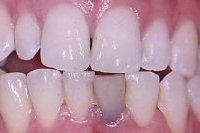

Ein seitlicher Oberkieferschneidezahn ist als sogenannter Zapfenzahn (angeboren) in die Mundhöhle durchgebrochen (Abb. 1). Nach orthodontischer Zahnbehandlung haben wir dem 16 Jahre alten Mädchen den Vorschlag gemacht, mittels zwei adhäsiv gelegten Kompositfüllungen und ohne Beschleifen den Zapfenzahn in einen natürlichen Schneidezahn umzuformen (Abb. 2).